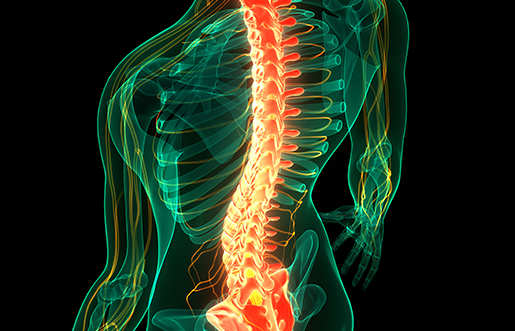

허리뼈(요추) 사이에는 디스크(추간판)라는 젤리 같은 구조물이 있어 충격을 흡수합니다.

그런데 나이가 들거나 무리한 동작으로 이 디스크가 밀려나와 신경을 눌러 통증을 유발하는 것이 허리디스크입니다.

📌 허리 협착증이란?

협착증은 척추관이 좁아져서 신경이 눌리는 질환입니다. 나이가 들수록 척추 주변 뼈와 인대가 두꺼워지고, 디스크도 조금씩 튀어나오면서

신경이 눌리는 공간이 점점 줄어들게 됩니다.

즉, 디스크보다 더 나이와 관련된 퇴행성 질환으로 보는 것이 맞습니다.

신경이 눌릴 때 나타나는 증상은 단순히 아픈 것 이상의 괴로움을 줍니다.

좌골신경이라는 길고 굵은 신경이 다리까지 이어지기 때문에, 허리 문제로 인해 다리까지 저리고 감각이 둔해질 수 있습니다.

특히 협착증은 혈액순환까지 제한되어 걷다 보면 다리가 터질 것처럼 아프고, 잠시 앉아 쉬면 괜찮아지는 ‘간헐적 파행’이라는 특징적인 증상도 보입니다.